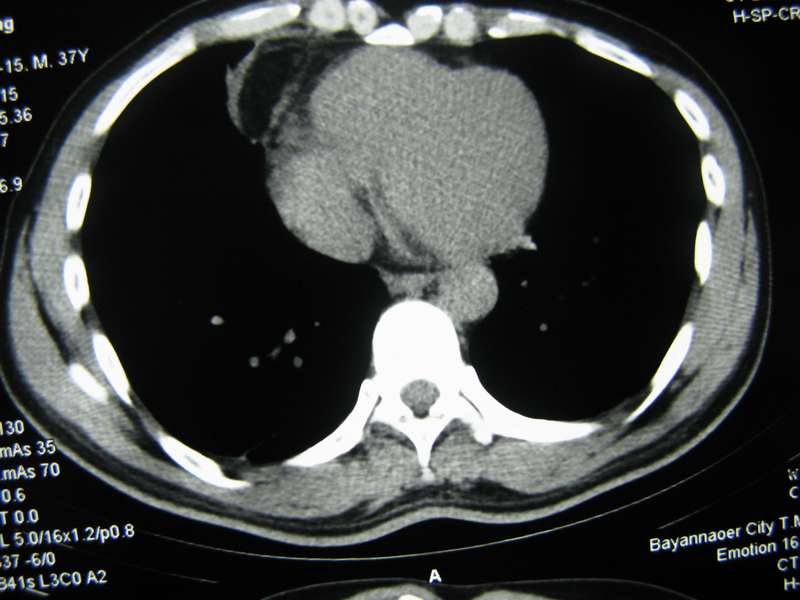

男,37岁,主述胸疼厉害,无咳嗽,无发热,血象也不高,病灶内ct值脂肪密度,右侧胸腔内少量积液,同道们考虑什么?谢谢!

两肺下叶基底段纤维灶,右肺下叶基底背侧相应胸膜肥厚,右肺中叶内侧段部分不张。前中下纵隔团块状脂肪影,随访除外胸腺脂肪瘤。

不除外膈疝。